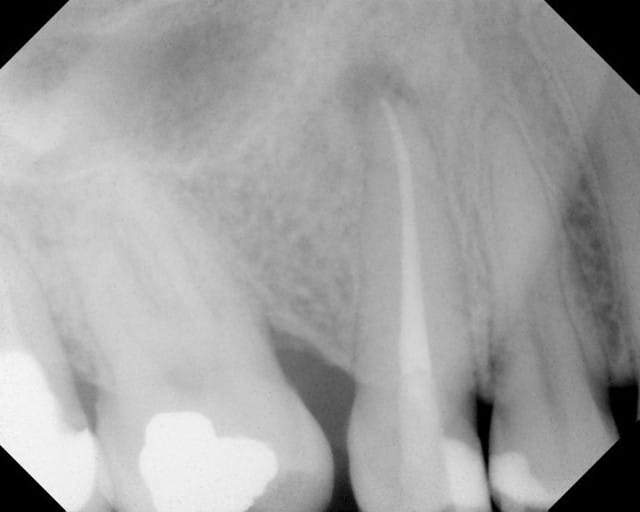

La double courbure en distal m'as donné du mal!

Pas de soucis particulier mais arthrite post op. Je crois que je vais me régler à 1 mm de l'apex radiologique désormais.

Ben oui, parce là, tu défonces le foramen à chaque fois. Sers-toi du localisateur et respecte ses indications.

Ca n'arrive pas à chaque fois. Comme ca c'est mieux ?

Un peu. Tu as tendance à ne pas savoir te retenir. Un obturateur précoce, en quelque sorte.

bon j'arrete le r40, une étape en moins

Et dans la foulée comme j'étais en forme.....

Tu fais comment ton obturation ? Lentulo pâte et monocone ?

Pas de lentulo. Scellement monocone ah+. Effectivement c'est le seul moment ou sur une dent mandibulaire la salive peut faire chier car j'enlève le lingua-fix pour la radio (optragate toujours en place).

D'un autre coté comme le résultat est reproductible il est rare de retirer les cones et de réinstrumenter.